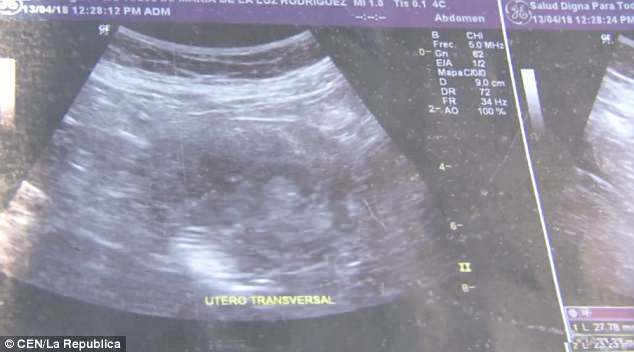

Η Μαρία Ντε Λα Λουζ έδειξε στους δημοσιογράφους υπερηχογραφήματα, τα οποία σύμφωνα με την ίδια επιβεβαιώνουν ότι είναι 6 μηνών έγκυος και περιμένει κοριτσάκι.

«Μου είπαν ότι είναι κορίτσι. Κοιτάξτε, μπορείτε να δείτε το πρόσωπό της», ανέφερε η 70χρονη γυναίκα από το Μεξικό.

Ένα από τα υπερηχογραφήματα της Μαρία Ντε Λα Λουζ.